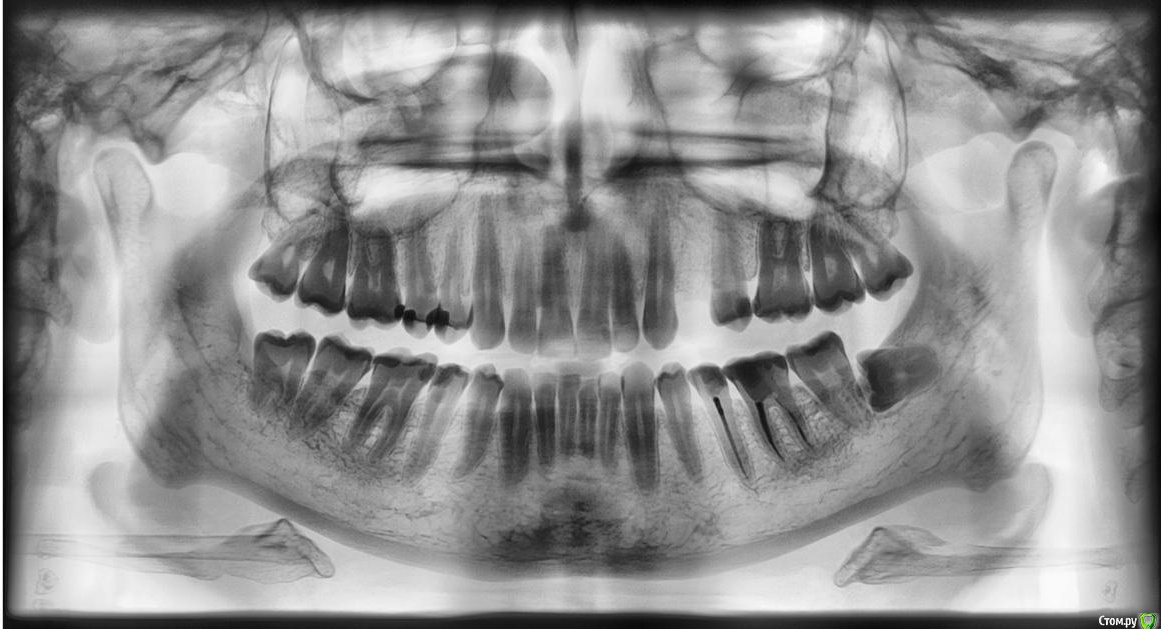

Два месяца назад был депульпирован нижний пятый зуб. Первый месяц было все хорошо.

После появились неприятные ощущения, покалывание, ощущение щекотания в кости у зуба.

На постукивания зуб немного реагировал в течение месяца. Боль не яркая, но глухая.

Две недели назад заложили лекарство.

Прошла неделя-поменяли лекарство, но при заложении его и уплотнении когда происходило надавливание внутри-боль отдавалась где-то в кости и немного в самом зубе.

Прошло два дня, появилось ощущения небольшого нарывания и ноющей боли. Сеичас в зубе лекарство, зуб не распломбирован-сверху просто снята частично пломба и внутрь заложено лекарство-сверху временная пломба.

Что это может быть такое?